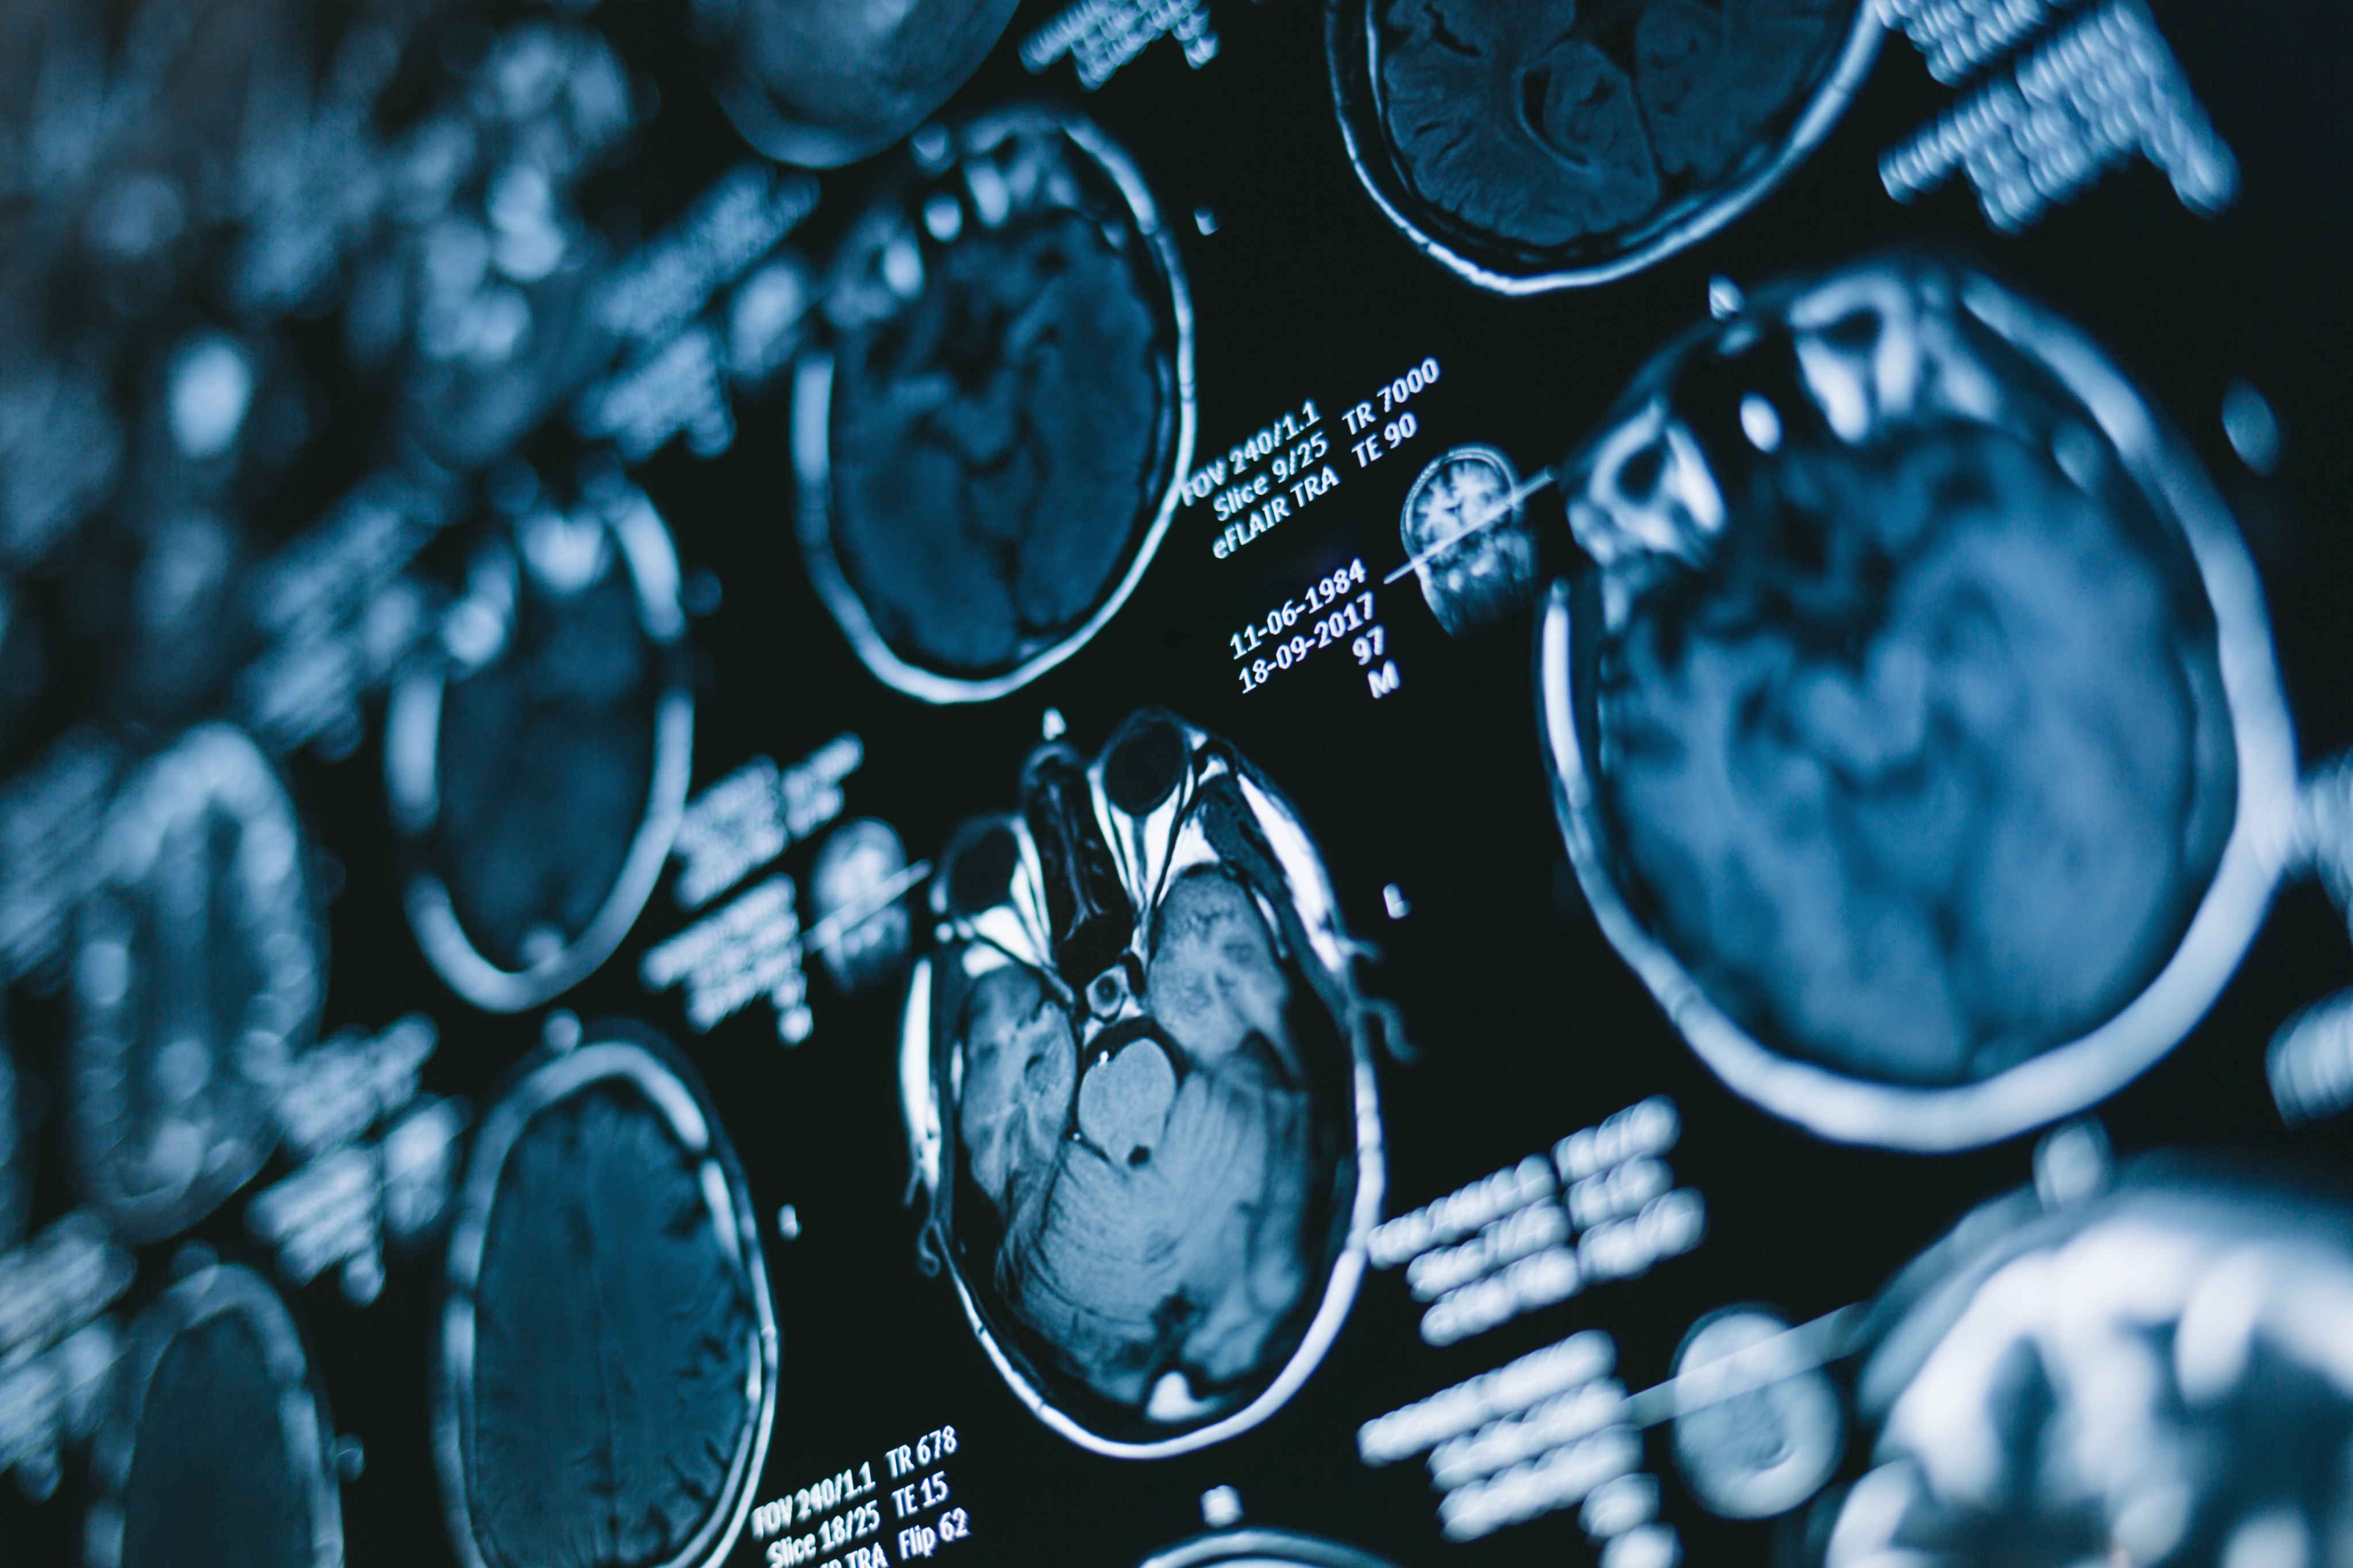

radiology imaging - types of imaging

Types of imaging